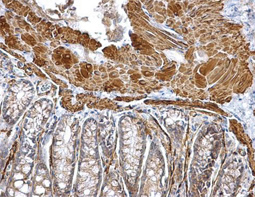

| 上皮-间质转化(EMT)是一个过程,在该过程中,大部分黏附和极化的上皮细胞获得了更多可移动的间质细胞的表型,EMT不仅促进胚胎发育过程中的型态发生,而且还促进肿瘤的侵袭和转移,病理性EMT与E-钙黏着蛋白(E-cadherin)阻抑有关,已被证明可促进肿瘤进展,据报导,几种致癌途径(例如: TGF-beta, Wnt/beta-catenin, integrins与Notch)通过细胞骨架重排和E-钙黏着蛋白阻遏物的激活来诱导EMT,包括Snail, Slug, SIP1, ZEB1和TCF3。 |